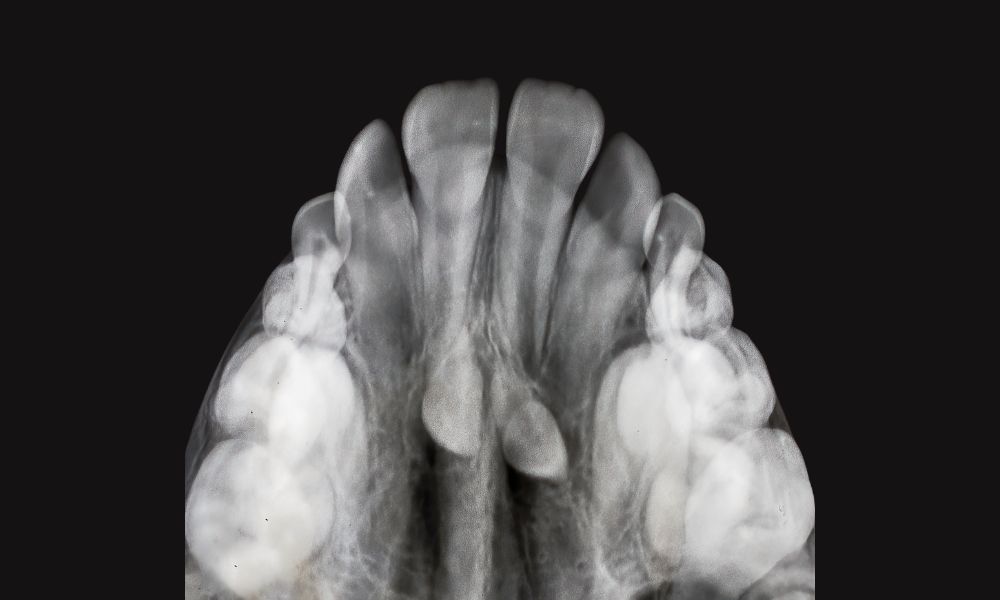

En esta condición, el paladar tiene forma de “V” o “gótica”. Normalmente, debería tener una forma ovalada. Los factores genéticos pueden causar el 30% de los casos.

El maxilar superior debe ser 5 mm más ancho que el inferior. En casos de paladar estrecho, esta diferencia puede ser mayor. Un estudio mostró la necesidad de expandir el maxilar superior en 11 mm.

Los síntomas incluyen mordida cruzada, apiñamiento severo y dientes inclinados hacia dentro. Estos problemas afectan la estética de la sonrisa. También pueden causar dolor en la articulación temporomandibular en el 20% de los casos.